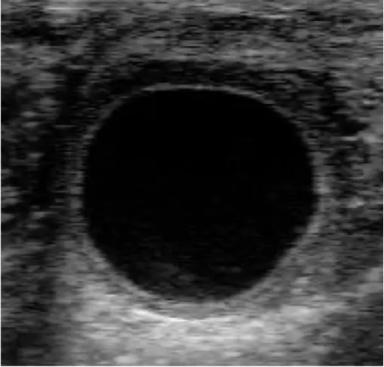

Определение супоросности на ранних сроках при помощи УЗИ!

593

И снова здравствуйте!

В прошлом посте мы разобрались с Ультразвуком и цветами реализации снимков.

Сегодня у меня есть для Вас интересный интерактив, конечно без призов, но думаю будет ...

Очень очень близко, 21 день супоросности)

В будущем выложу пост с размерами по срокам супоросности)